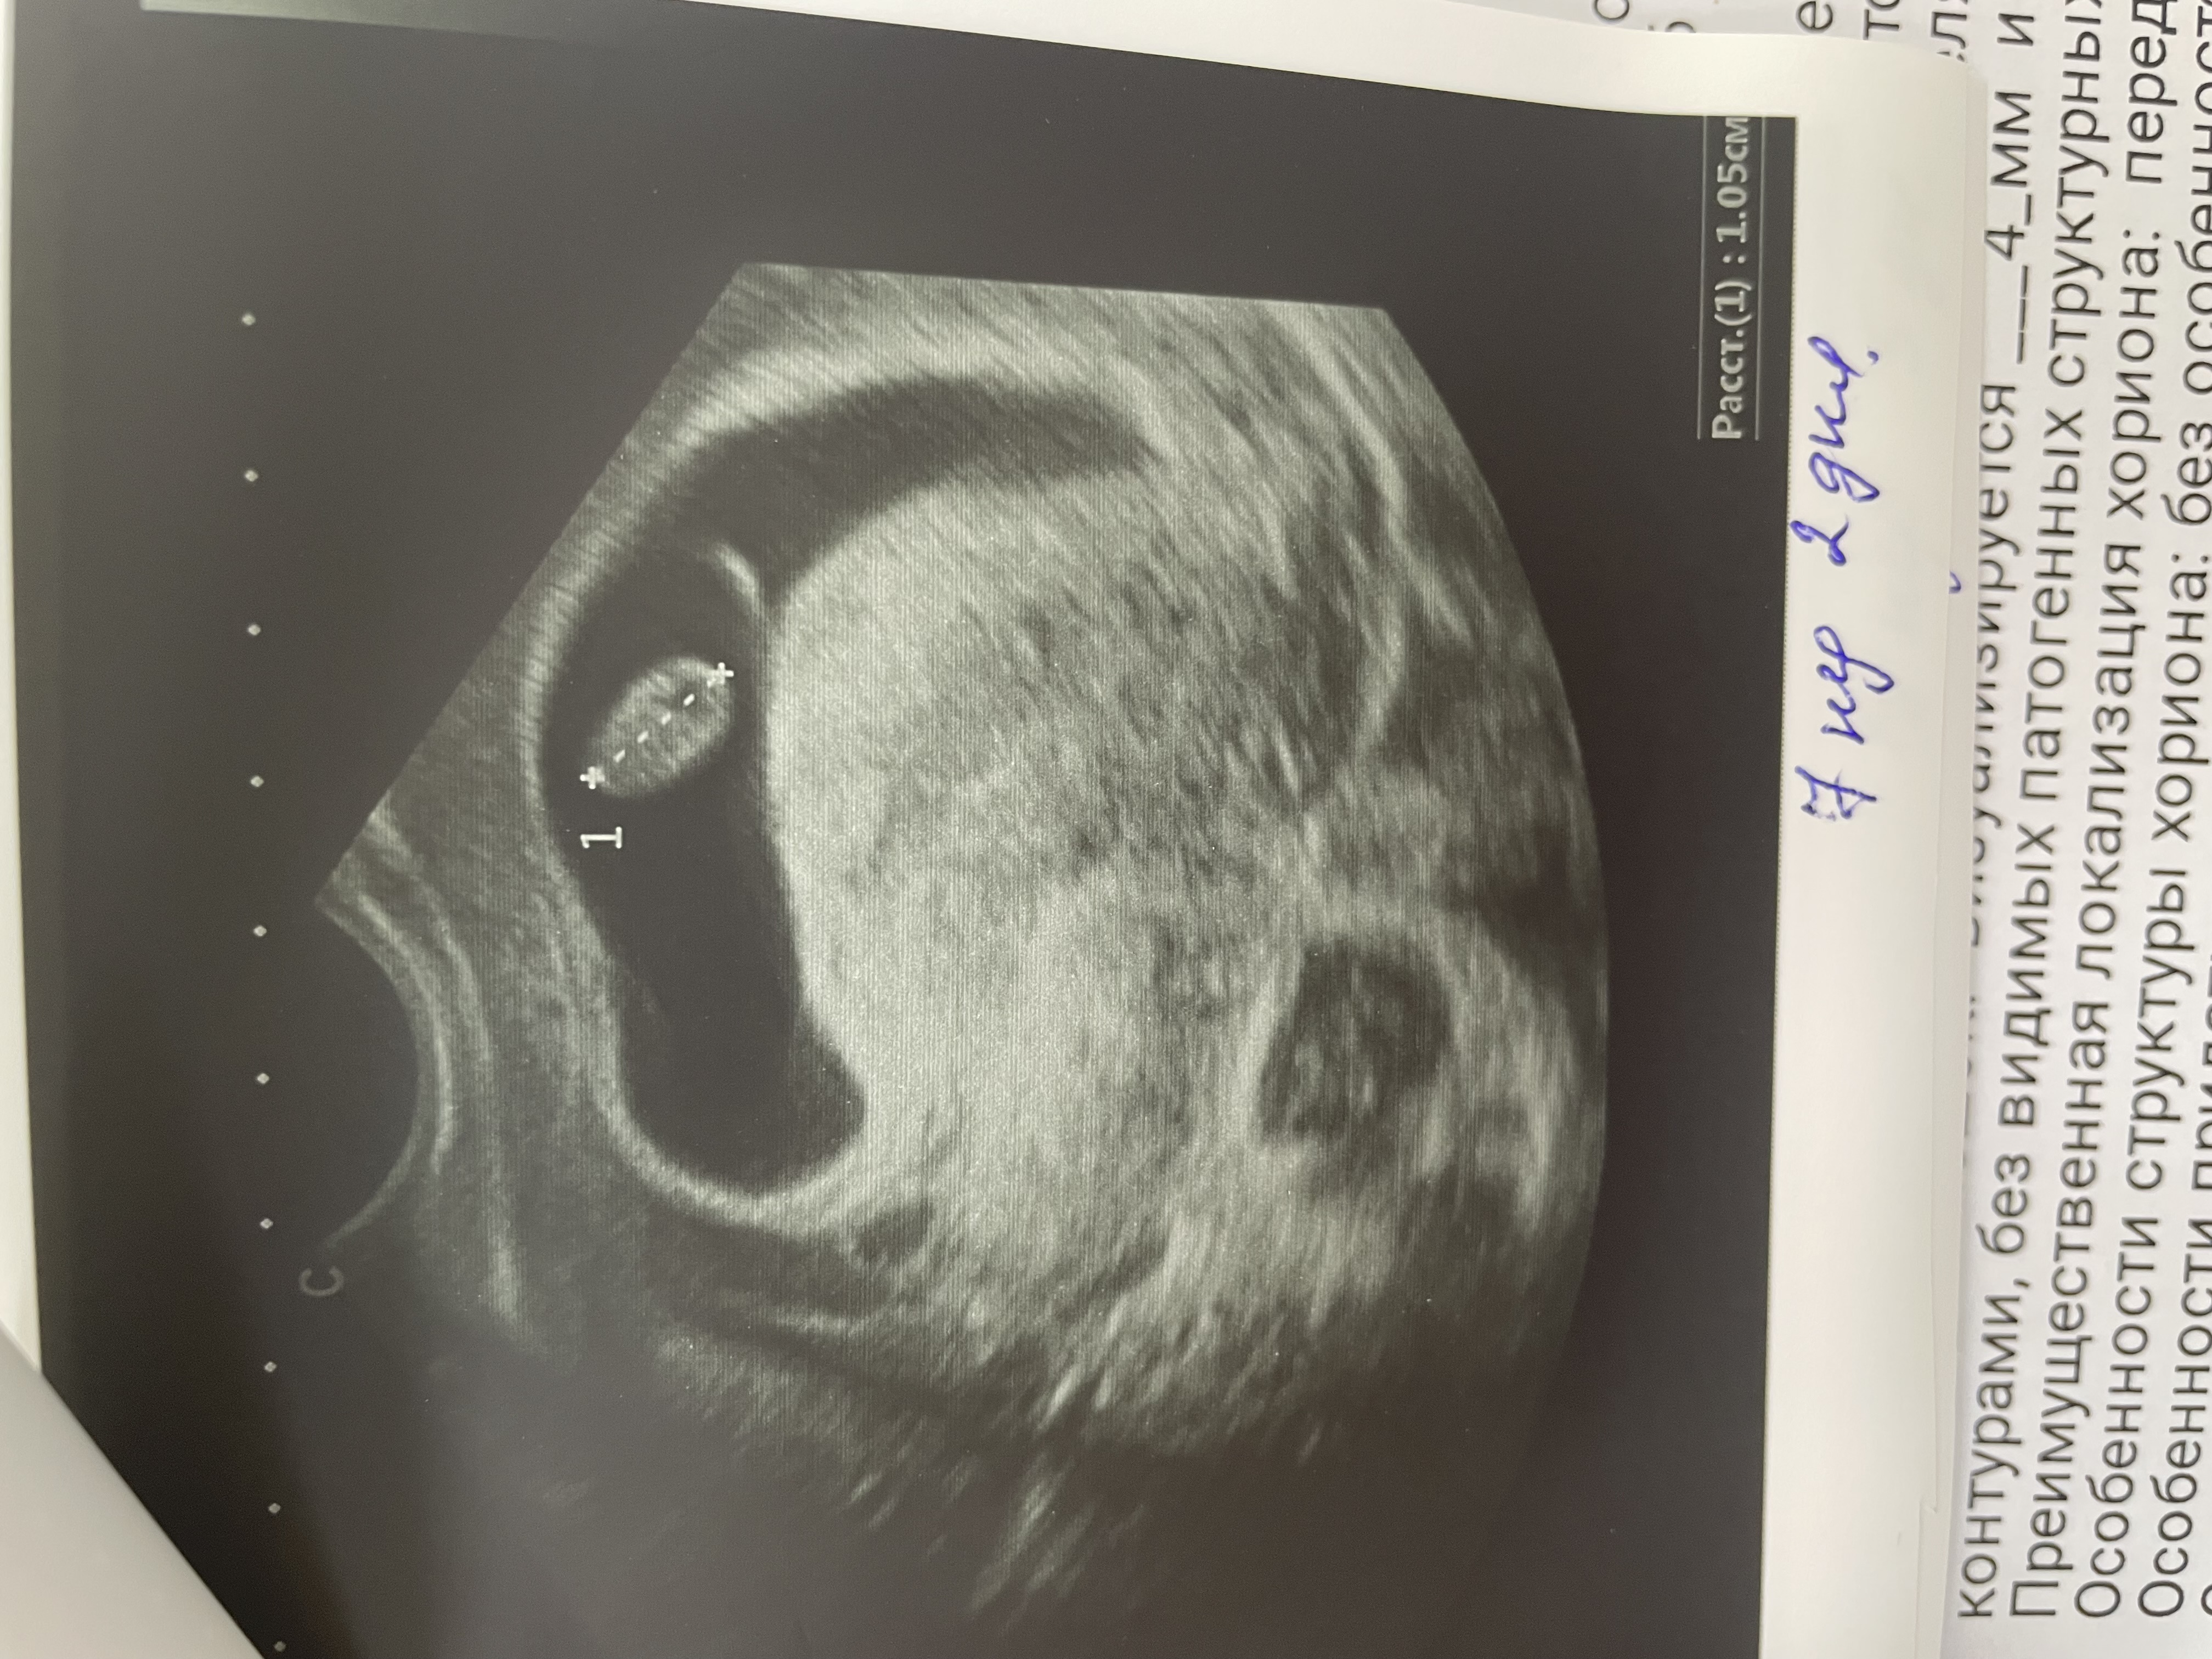

Растут мои крошки 💕✨🤰

у меня двойня!!!!!!! Вторая двойня подряд